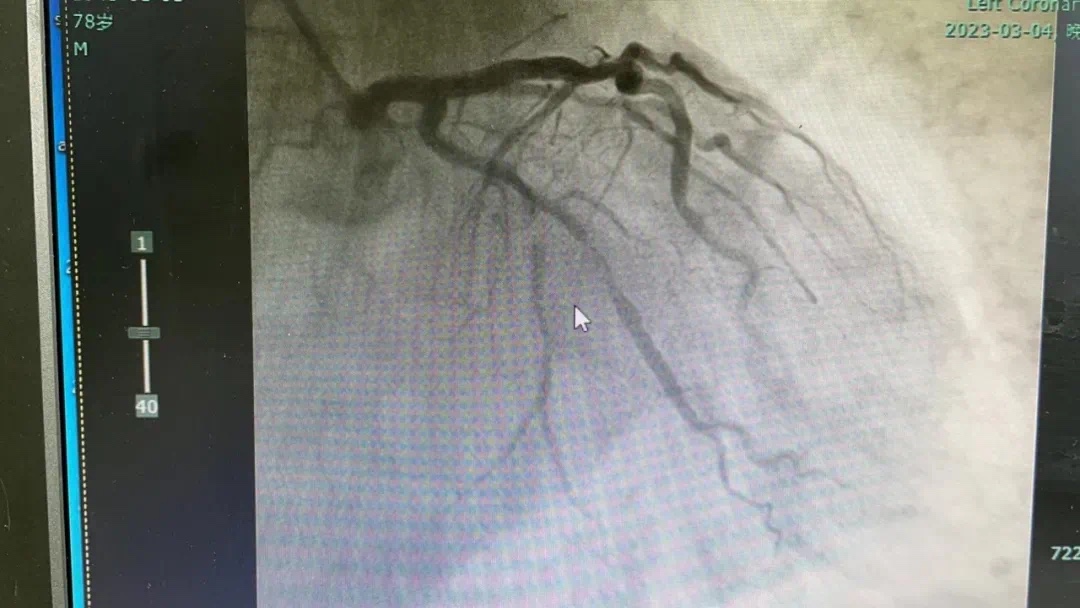

副主任何涛、医师熊俊锋、护士张梅梅顾不上休息,立刻投入到第三次抢救中。胸痛中心团队心内科与急诊科无缝衔接,23点26分在导管室开通堵塞血管,又成功救治一名急性心肌梗死患者。患者张某送至导管室施行急诊冠脉介入治疗,经过快速的术前准备,以mini Crush术式于回旋支远段植入波科冠脉支架一枚,再于钝缘支中段至回旋支中段植入Firebird2冠脉支架一枚。患者症状大幅缓解。零点42分手术结束,复查患者血压、心率正常后将患者送回病房。

术前、术后图片如下